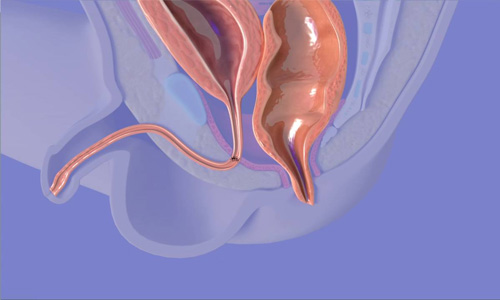

Ano-rectal Surgery

Erat ipsum justo amet duo et Anorectal surgery is a surgical procedure to treat anal and rectal conditions and cancer, generally by the removal (resection) of a portion..